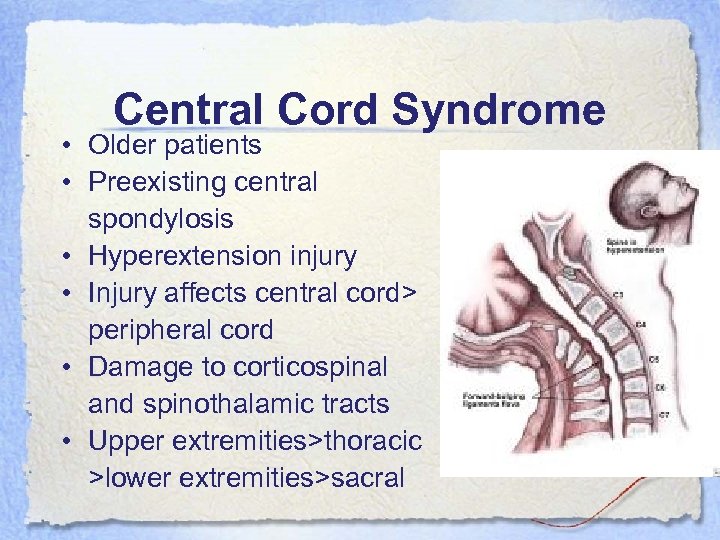

Central Cord Syndrome • Older patients • Preexisting central spondylosis • Hyperextension injury • Injury affects central cord> peripheral cord • Damage to corticospinal and spinothalamic tracts • Upper extremities>thoracic >lower extremities>sacral

Central Cord Syndrome • Older patients • Preexisting central spondylosis • Hyperextension injury • Injury affects central cord> peripheral cord • Damage to corticospinal and spinothalamic tracts • Upper extremities>thoracic >lower extremities>sacral